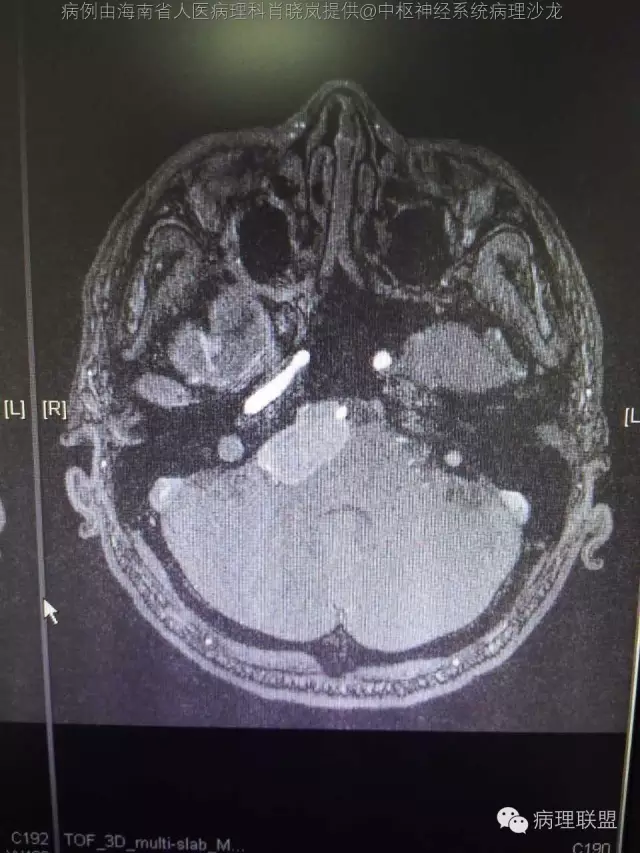

男,36岁。右面部麻木1月余。手术所见:右CPA区见5Ⅹ4cm肿块,灰褐色,血供丰富,质韧,界清。临床诊断:右侧桥小脑角区占位:脑膜瘤。大体检查:灰黑色碎组织一堆,大小2.5Ⅹ2.5x0.5cm,免疫S100,HMB45阳性。Ki67指数低。(病例由海南省人医病理科肖晓岚提供,致谢!)

@海南省人医病理科肖晓岚 影像也是符合黑色素相关肿瘤,可请影像专业的老师分析一下CT结合MR对产生黑色素的病变还是具有一定的特征性的,本例黑色素含量似乎不太多,所以跟脑膜瘤差不太多了,需要请影像老师分析!